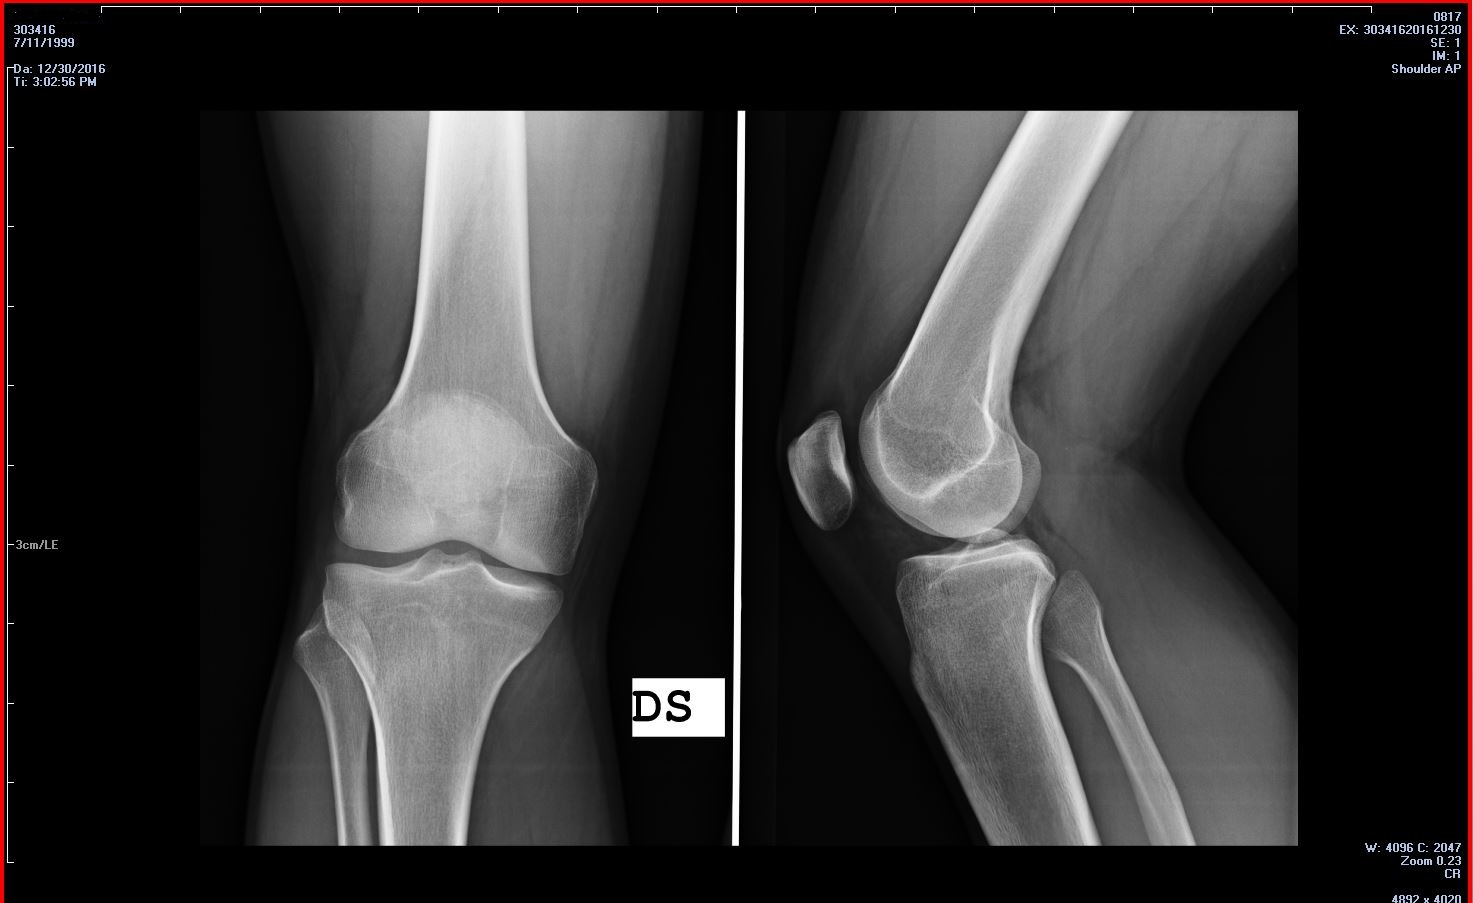

Talvolta ha un forte dolore interno al ginocchio che si manifesta saltuariamente e che si accentua in seguito ad attività sportiva (bicicletta). Dopo esserci rivolti al medico di base abbiamo effettuato sia la radiografia che la risonanza magnetica. Adesso siamo in attesa di visita specialistica, ma vorrei cogliere l' occasione per chiedere quì un vostro parere.

Pubblico l' immagine della Rx al ginocchio destro, se dovesse servire, dispongo anche delle immagini della Risonanza, che per brevità non posto adesso.

Esito RX:

"Non si rilevano segni di lesioni osteoarticolari, nè si apprezzano immagini riferibili a calcificazioni dei tessuti molli periarticolari".